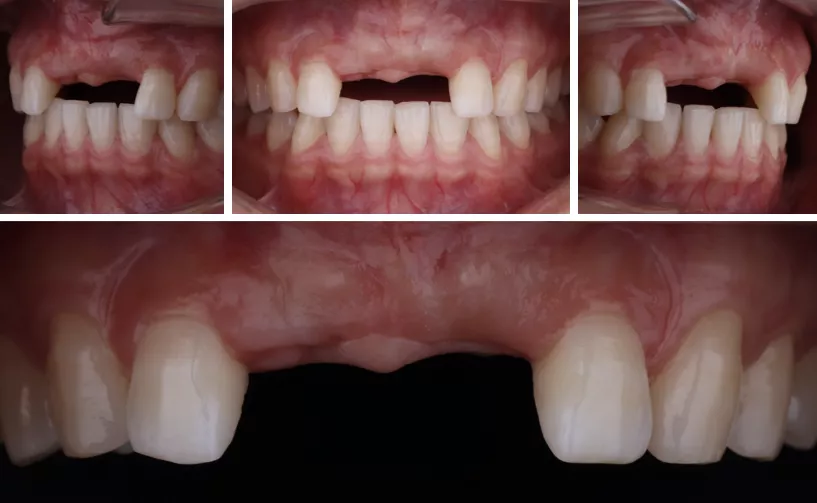

定期检查,评估植体及牙龈情况

·     佩戴两个月后复查。

·     检查唇齿关系。

修复体试戴及粘接

半年后复查

·       患者在历经一年多的前牙种植修复治疗后,得到了总体较好的功能修复和美观效果。病历总体达到了预期的治疗效果,患者较为满意。

·       稍显不足的是在患者佩戴了最终修复体后,龈缘高度的对称性还存在一些偏差。并且右侧袖口相比左侧的效果稍显不足。由于患者在治疗期间由于工作变动和疫情的因素,临时牙佩戴时间较长发生了几次断裂,损伤了穿龈袖口部软组织并且影响了牙龈塑形,可能是导致最终效果稍有偏差的主要因素。随之进行额外的软组织手术将卵圆形牙齿变为方圆也许会获得更加的红白美学效果。